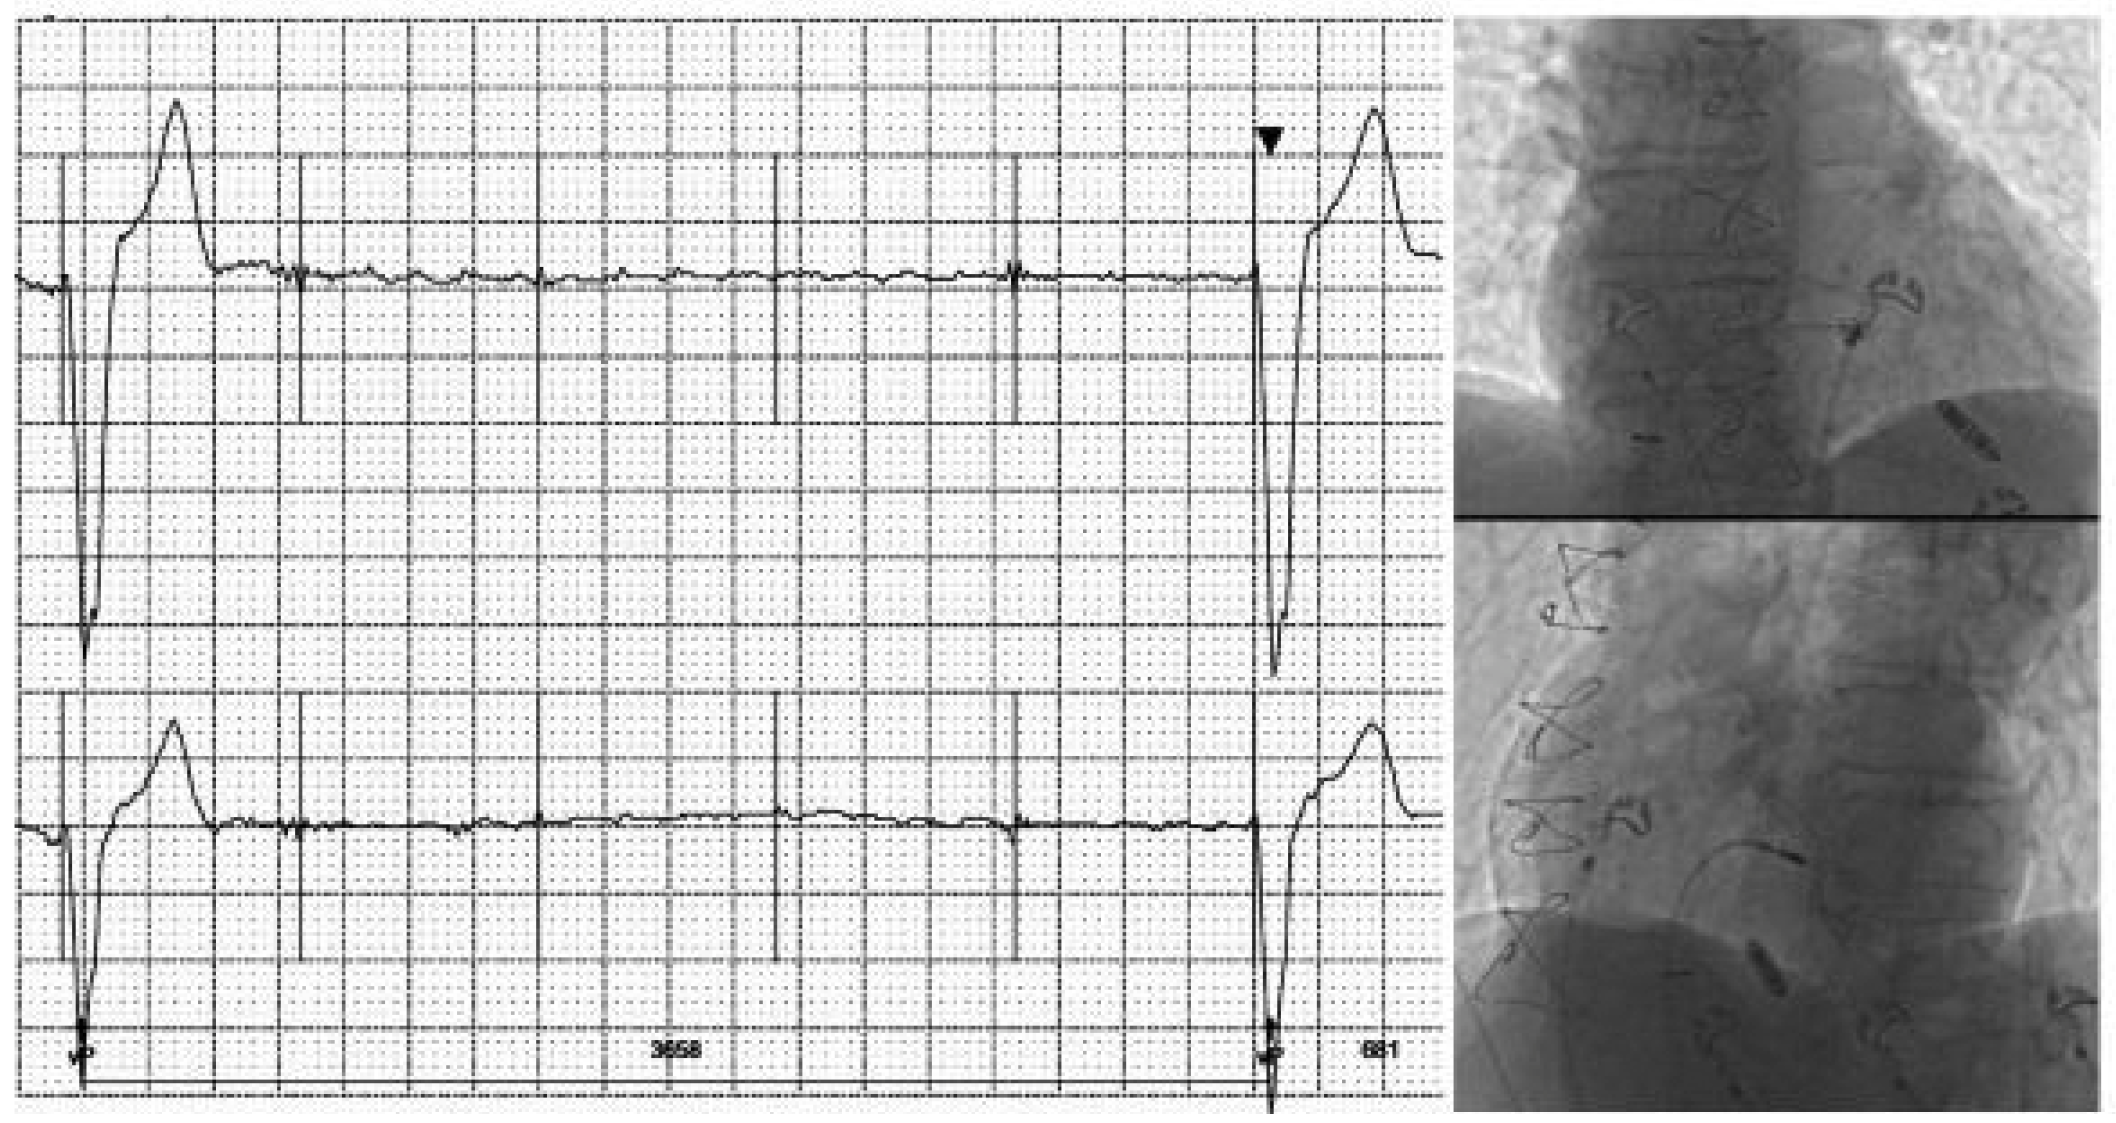

A 66-year old female was hospitalized in our Cardiovascular Department for a first episode of syncope. Clinical history revealed smoking and hypercholesterolemia. The baseline ECG showed repetitive non-sustained ventricular tachycardia (VT) of rather narrow QRS duration originating from the infero-basal interventricular septum (IVS) or from the right moderator band (Figure 1). A coronary angiography revealed a 50–70% stenosis of the left main coronary artery treated with the implantation of an active stent.The echocardiography was non-contributive, but the cardiac MRI revealed a localized thickening of the inferior IVS (Figure 2A) with hyperintense inhomogeneous appearance on T2-weighted images (Figure 2B) confirmed by elevated T2 values (60 ms, normal values <55 ms; Figure 2D) and T1 values (1184 ms, normal values <1050 ms; Figure 2C); the high signal intensity on late gadolinium enhancement (LGE, Figure 2E-2F) was indicative of a large interstitial space secondary to edema (high T2 and T1 values) and hypervascularization. The following differential diagnoses were considered: cardiac sarcoidosis, metastatic tumor or infectious disease. Endomyocardial biopsy samples taken from the IVS did not show any malignant cells or granuloma. An electrophysiological study did not show any susceptibility to sustained ventricular arrhythmias. The unexplained 8-Kg weight lost over the past year in a smoker patient raised the suspicion of malignancy. An 18FDG-PET scan performed after a 24-hour carbon hydrate free diet revealed a focal hypermetabolic activity within the IVS at the site of LGE (Figure 2G). Interestingly, a hypermetabolic nodule in the upper lobe of the right lung (Figure 2H) together with active paratracheal lymph nodes were suggestive of a metastatic lung cancer, that was confirmed by cytoponction of paratracheal lymph nodes (non-small cell lung cancer: NSCLC). The patient started a combination chemotherapy with carboplatin and pemetrexed and now is followed by the oncologists and the cardiologists.

Conclusions: this clinical case represents an unusual manifestation of lung cancer (NSCLC) with cardiac metastasis presenting with repetitive non-sustained ventricular tachycardia. In this patient, cardiac MRI allowed to detect the cardiac metastasis and was useful to guide the endomyocardial biopsy and the elettrophysiological study.